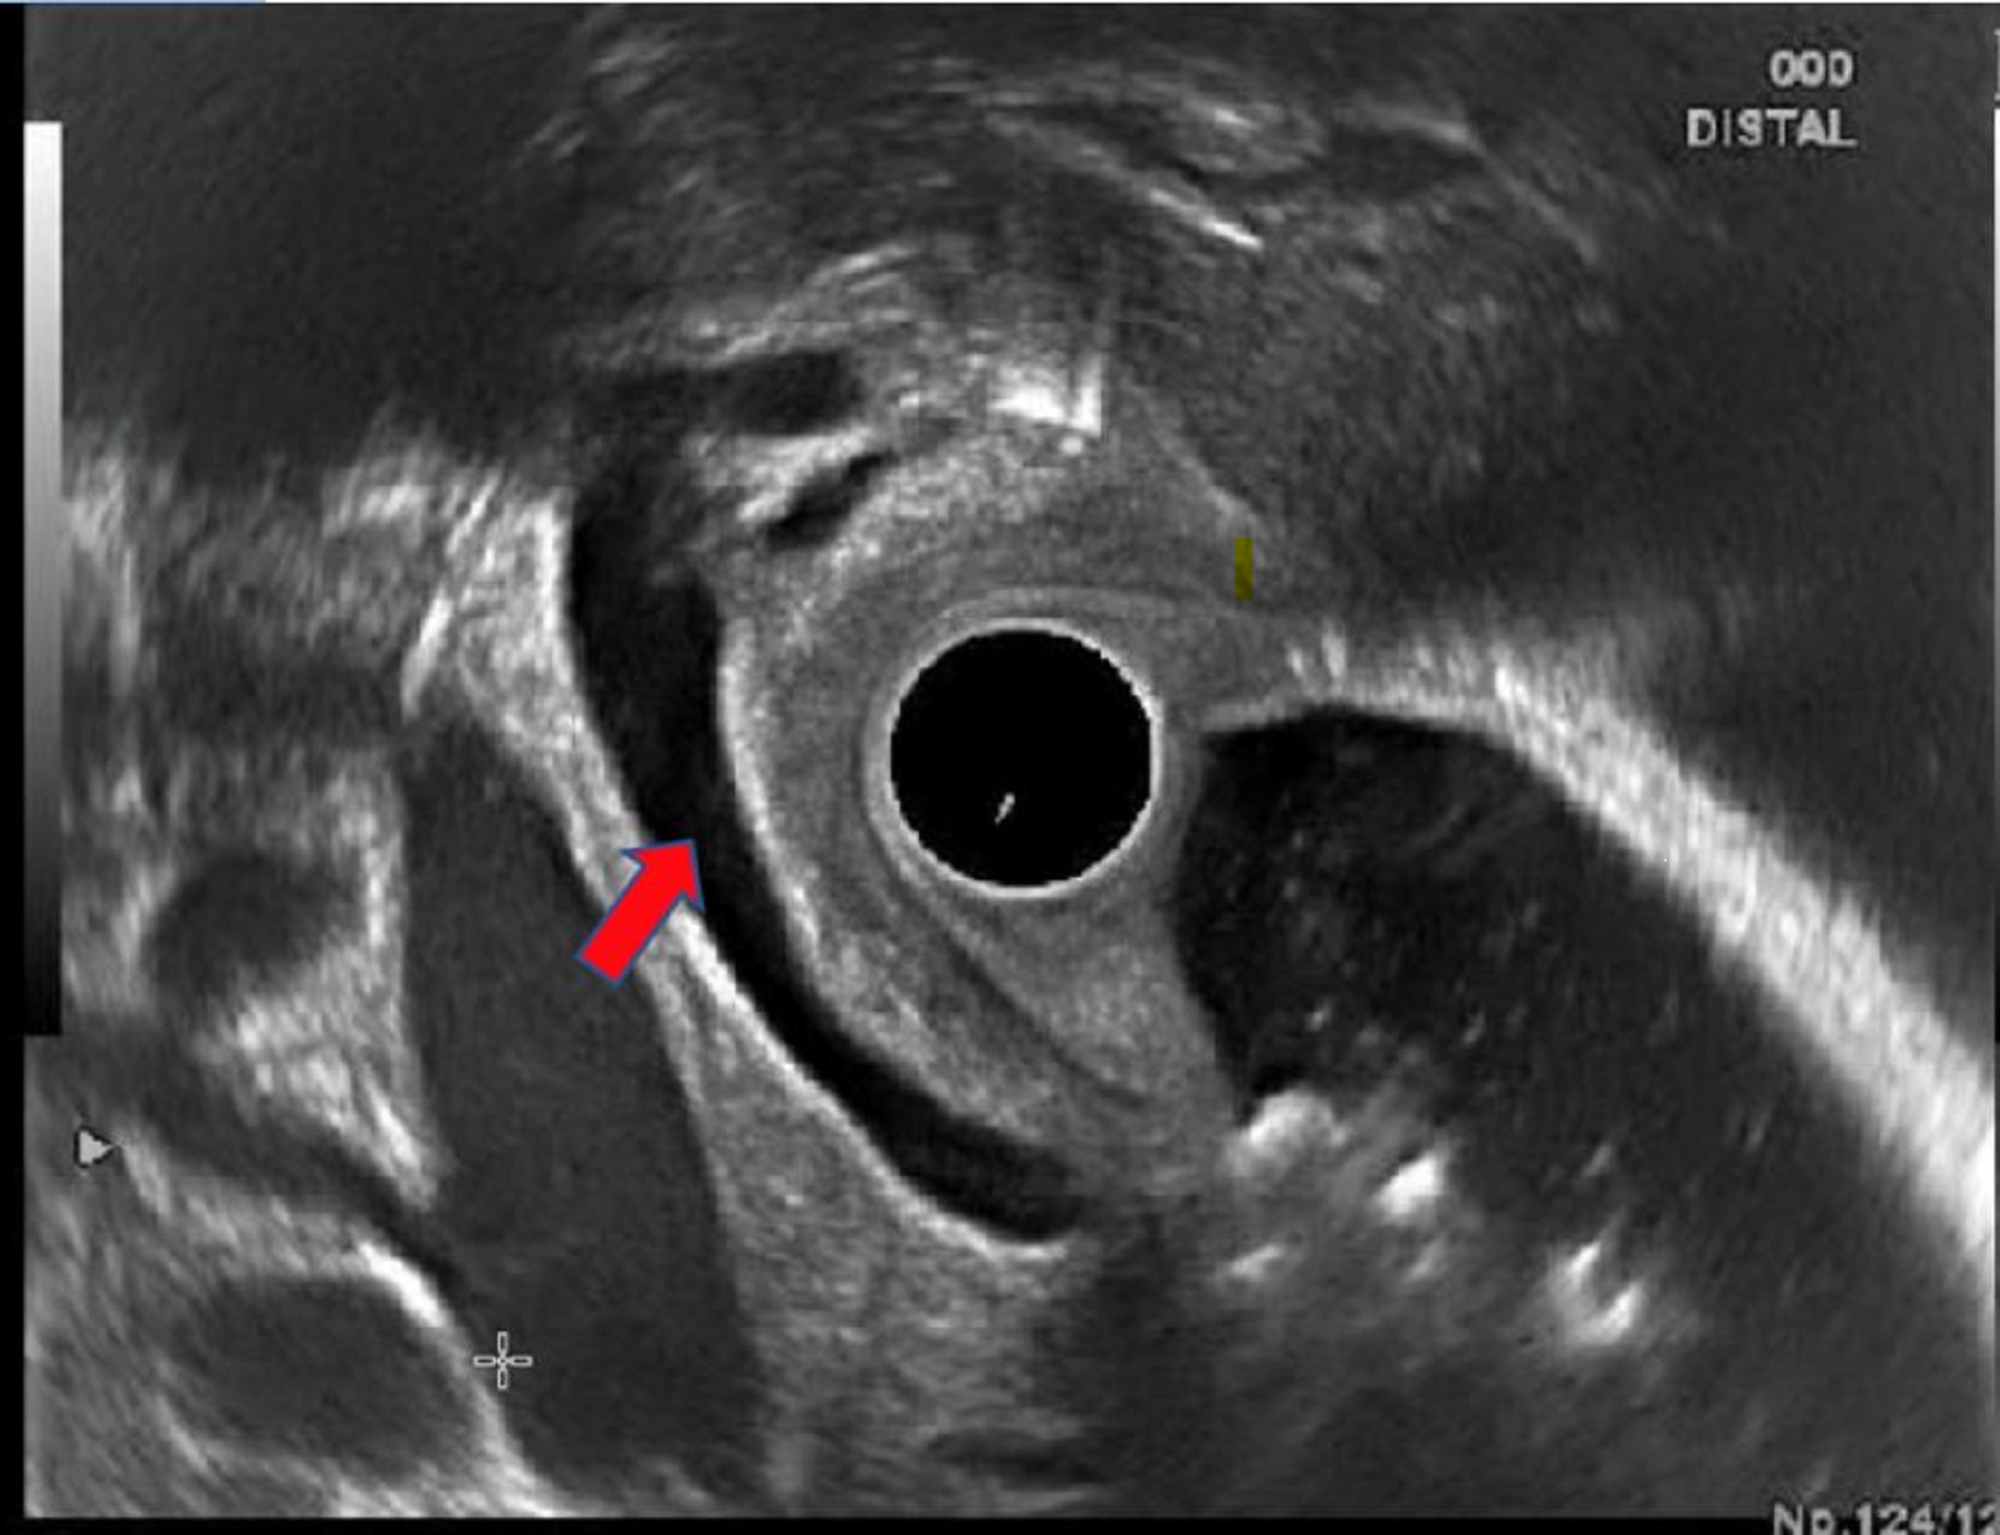

Radial endoscopic ultrasound showing grossly dilated common bile duct Endoscopic Ultrasound Dilated Bile Duct Prospective cohort of consecutive patients with biliary dilatation & non diagnostic computed tomography (ct) and /or magnetic resonance. Endosonography or endoscopic ultrasound (eus) is a helpful modality in this scenario to detect lesions producing biliary. Of 29,920 upper gastrointestinal eus procedures performed, 840/29,920 (3%) were for unexplained cbd. Biliary dilatation without obvious etiology on cross sectional imaging warrants further. In. Endoscopic Ultrasound Dilated Bile Duct.

Radial endoscopic ultrasound showing grossly dilated common bile duct Endoscopic Ultrasound Dilated Bile Duct Endosonography or endoscopic ultrasound (eus) is a helpful modality in this scenario to detect lesions producing biliary. Prospective cohort of consecutive patients with biliary dilatation & non diagnostic computed tomography (ct) and /or magnetic resonance. Biliary duct dilatation is a common finding in clinical practice and is often incidental. Common bile duct (cbd) dilation is a frequent indication for eus.. Endoscopic Ultrasound Dilated Bile Duct.